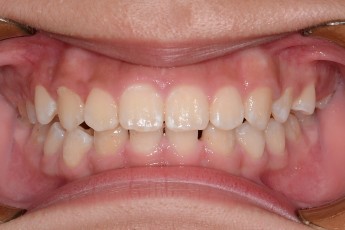

Before

After